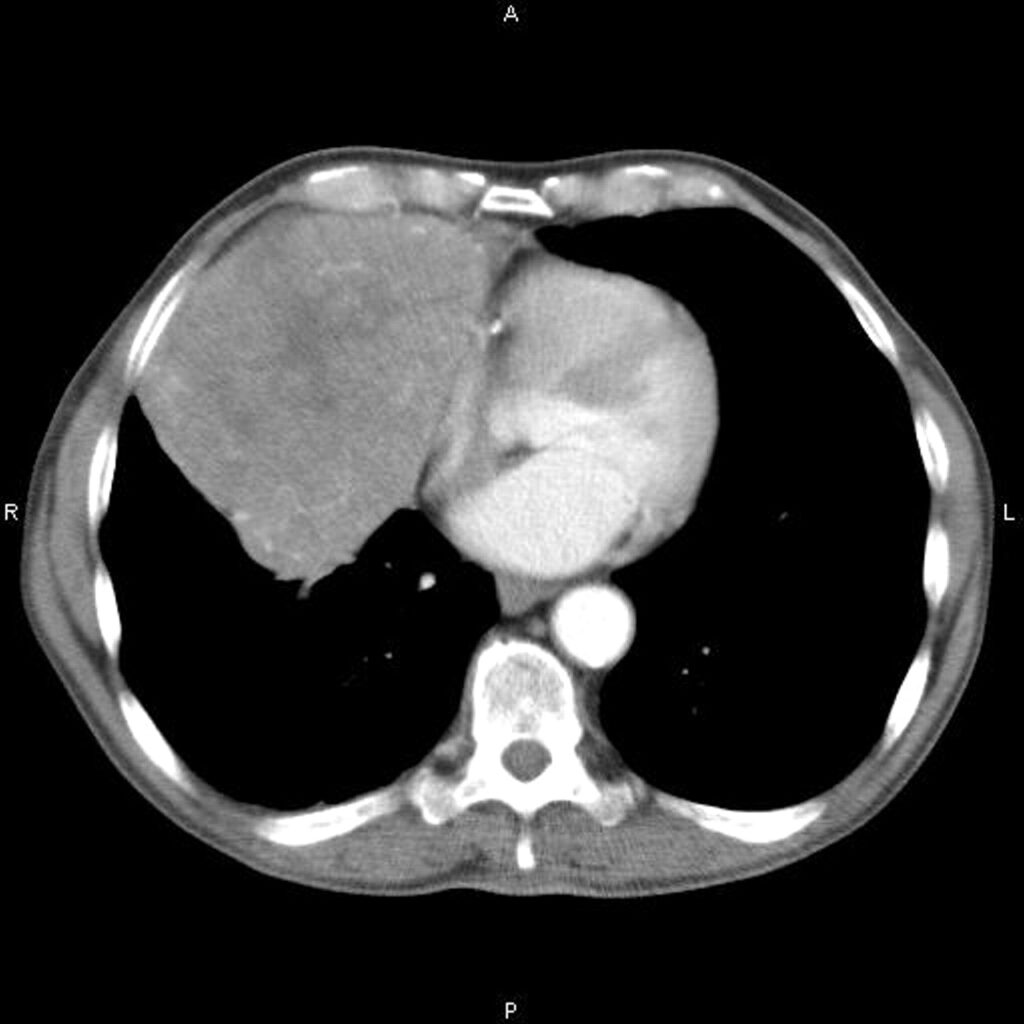

La tomografía computarizada (TC) juega un papel crucial en la evaluación y manejo de las masas mediastínicas. Este tipo de imagenología permite una visualización detallada de la masa y sus características, incluyendo su tamaño, forma, ubicación y relación con las estructuras circundantes. La TC es esencial para planificar el tratamiento, ya que proporciona información sobre la extensión local de la masa y si hay infiltración en tejidos vecinos.

La resonancia magnética (RM) es particularmente útil para la evaluación de estructuras mediastínicas complejas. Ofrece una delineación detallada de las estructuras hilares y permite distinguir entre vasos sanguíneos y masas de manera más precisa que la TC. Esto es importante para diferenciar las características de la masa y para planificar intervenciones quirúrgicas con mayor precisión.